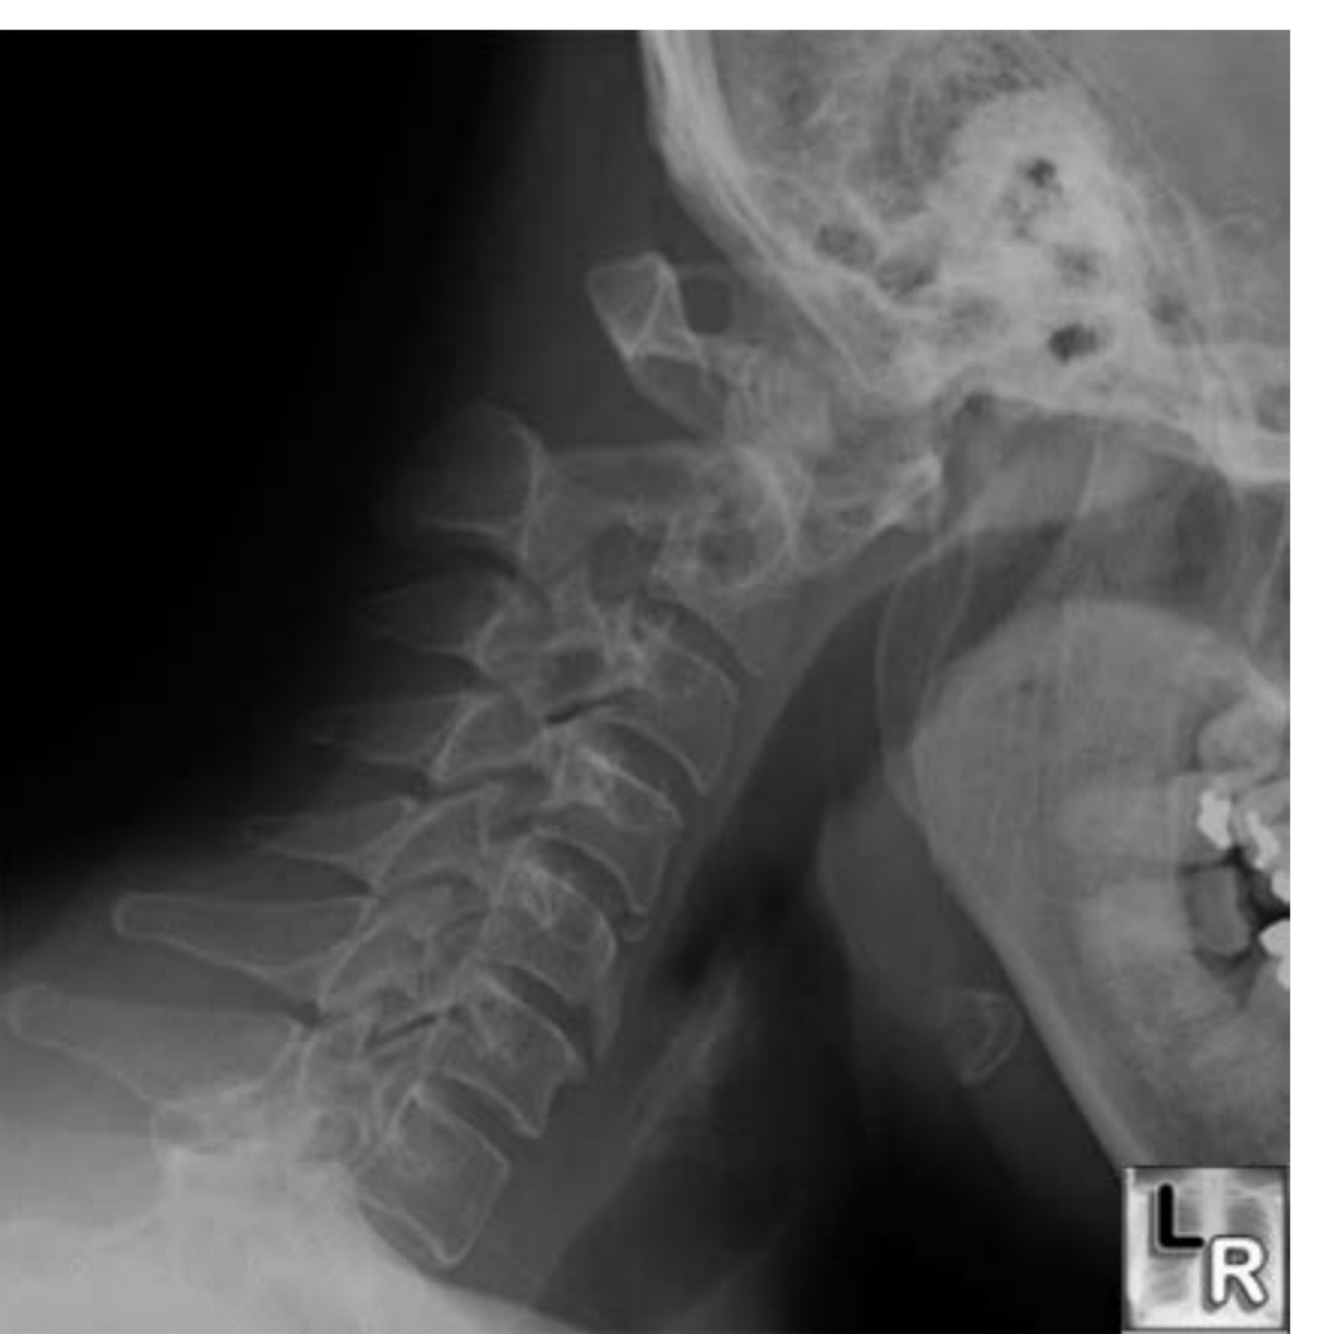

What does her c spine X-ray show? see Figure 5.5

Lateral radiograph of the neck with the head in flexion shows an increased distance between the anterior border of the dens and the posterior border of the anterior tubercle of C1. This “pre-dentate space,” should be less than 3 mm in the adult. Also there is forward suluxation of C1 on C2.

Mainly two types of changes might be seen: Atlanto-axial subluxation and

sub-axial subluxation.

Atlanto-axial subluxation

• Anterior: Most common (80%) finding in rheumatoid arthritis involving the neck, where C1 vertebra is moved forward on body of C2 vertebra due to damage to transverse ligament and can cause spinal cord compression by odontoid peg. Subluxation occurs when distance between atlas and odontoid is > 4 mm in adults and > 3 mm in children.

It is best seen in lateral neck X-ray with neck flexion (which makes

subluxation worse).

• Posterior: occurs in 5% of the patients and is due to destruction of

odontoid peg, which causes backward movement of C1 vertebra over C2 vertebra. It is best seen in lateral X-ray with neck extension, which makes the condition much worse.

- sub-axial subluxation It is not very common, occurs below C2 level, and can cause fixed flexion Deformity due to ankylosis and osteoporosis.